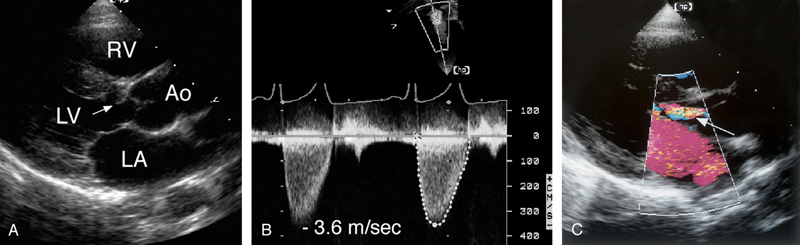

فحوصات تشخيصية لبعض امراض القلب والشرايين التاجية